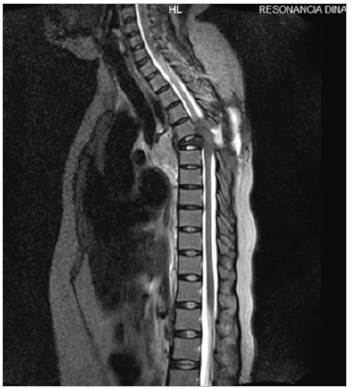

Mujer de 44 años con antecedente de artritis reumatoide. Inició hace cuatro años con dolor en región dorsal y lumbar, pérdida de peso no significativa, sin fiebre, parestesias y debilidad progresiva en miem bros inferiores hasta llegar a la inmovilización. A la exploración física paraplejia de miembros inferiores y reflejos osteotendinosos disminui dos, sin adenomegalias ni masas. Laboratorios sin anormalidades. La resonancia magnética de columna dorsal y lumbar mostró lesión ósea blástica en T5 que afecta cuerpo vertebral, pedículo, apófisis transversa y unión costo vertebral derecha condicionando disminución del diáme tro intervertebral (Figuras 1 y 2). Biopsia vertebral con hallazgos de osteomielitis crónica asociada a estructuras micóticas compatibles con coccidioides (Figura 3). Recibiendo anfotericina b desoxicolato durante dos semanas, hidratación intravenosa, presentando mejoría, egresándose con itraconazol y control por infectología. La coccidioidomicosis es una infección fúngica capaz de producir osteomielitis siendo la columna lumbar el sitio principal, pudiendo complicarse con abscesos paravertebrales 1,2.